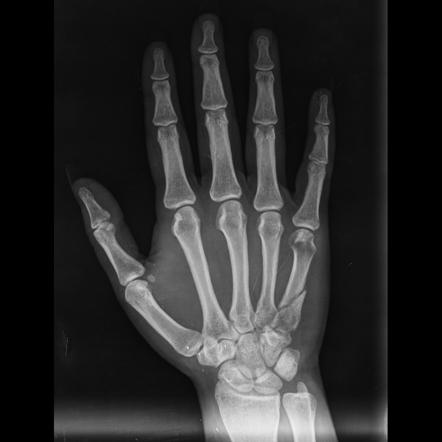

Les fractures des os métacarpiens, les os longs de la main reliant les doigts au poignet, sont des blessures courantes souvent causées par des chutes, des activités sportives ou des traumatismes directs.Ces dernières années, des avancées significatives dans la technologie médicale ont conduit au développement de plaques de verrouillage métacarpiennes, révolutionnant le traitement des fractures de la main.Ces implants innovants se sont révélés pro

résultats insuffisants en offrant une meilleure stabilité, une guérison plus rapide et de meilleurs résultats pour les patients par rapport aux méthodes de traitement traditionnelles.Dans cet article, nous explorons les avantages et les techniques chirurgicales associées aux plaques de verrouillage métacarpiennes, ainsi que les progrès qui ont encore amélioré leur efficacité.

Les fractures métacarpiennes peuvent varier en gravité et en localisation, affectant différentes parties de la main.Ils sont généralement classés en plusieurs types, notamment:

Les plaques de verrouillage métacarpiennes représentent une avancée majeure dans le traitement des fractures de la main.Ces plaques sont spécialement conçues pour fournir une fixation et un soutien stables pendant le processus de guérison.

Plaques de verrouillage sont uniques en ce qu'ils ont des trous de vis avec filetage interne, permettant aux vis de se verrouiller dans la plaque, créant une connexion plus sûre.